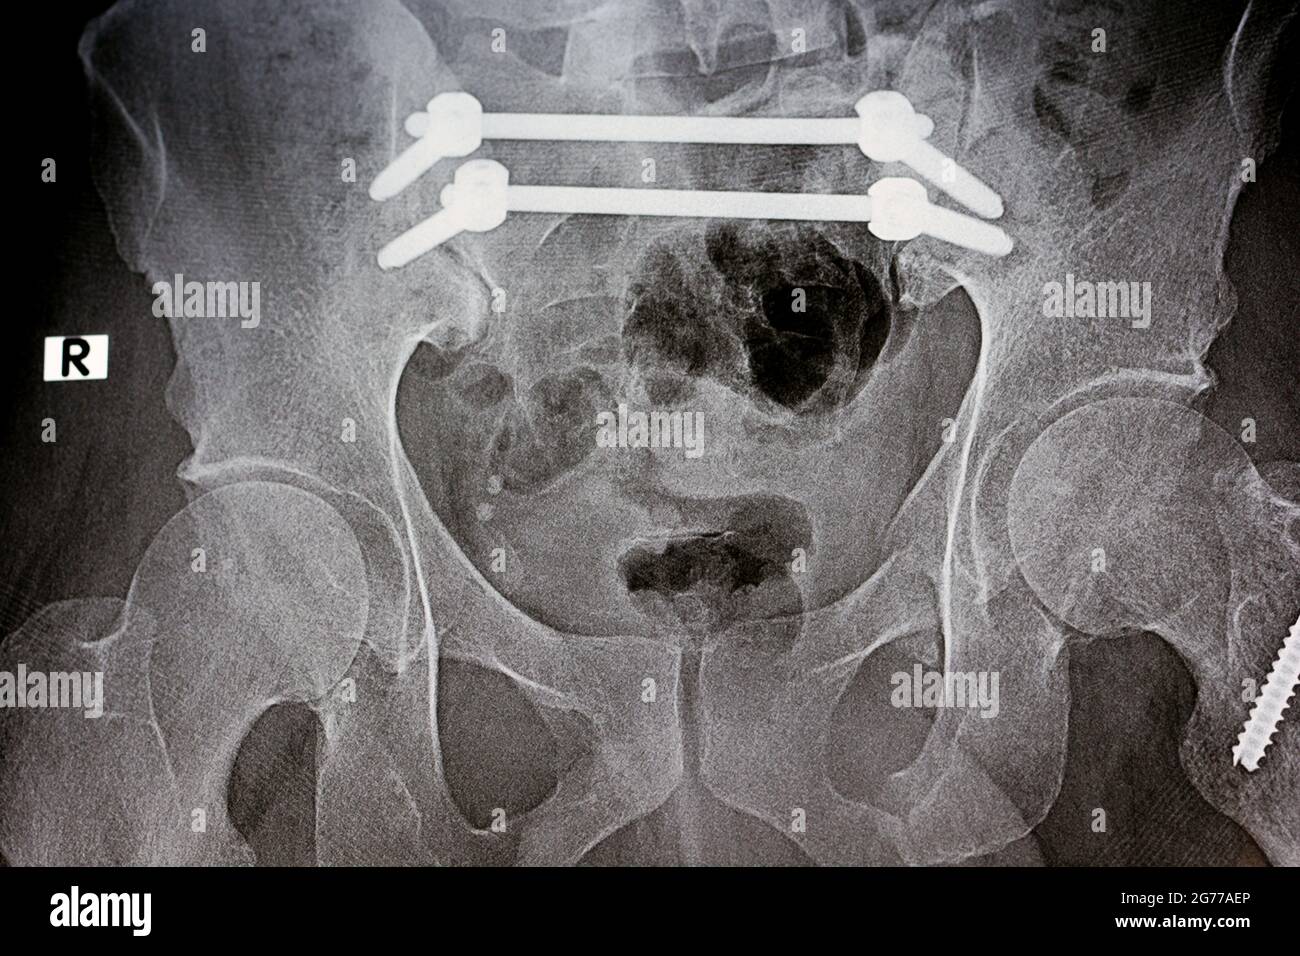

Sacrum Fracture X Ray . An insufficiency fracture is a subtype of stress fracture that occurs in bones with underlying structural weakness, most commonly due to osteoporosis. Diagnosis can made with pelvis radiographs but. Sacral insufficiency fractures are a subtype of stress fractures, which are the result of normal stresses on abnormal bone, most frequently seen in the setting of osteoporosis. Suspect sacral fractures in patients with pelvic ring injuries; According to the consensus, the best way to approach a patient with a suspected neurological impairment associated with a. The sacrum and coccyx lateral view is utilized to demonstrate the most distal region of the spine in a lateral position. There are several classification systems for sacral fractures, but the most commonly employed are the denis classification and subclassification systems, and. Perform a complete neurologic assessment as the presence of neurologic deficits will require advanced imaging.